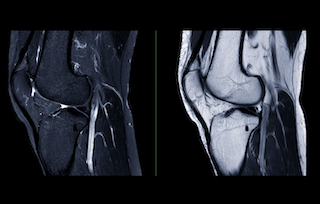

Do Ligaments Really Heal?

“You tore a ligament. Ligaments don’t really heal.” This statement is still commonly heard in clinics and gyms. Ligaments do have limited blood supply, but does that mean they cannot heal at all?